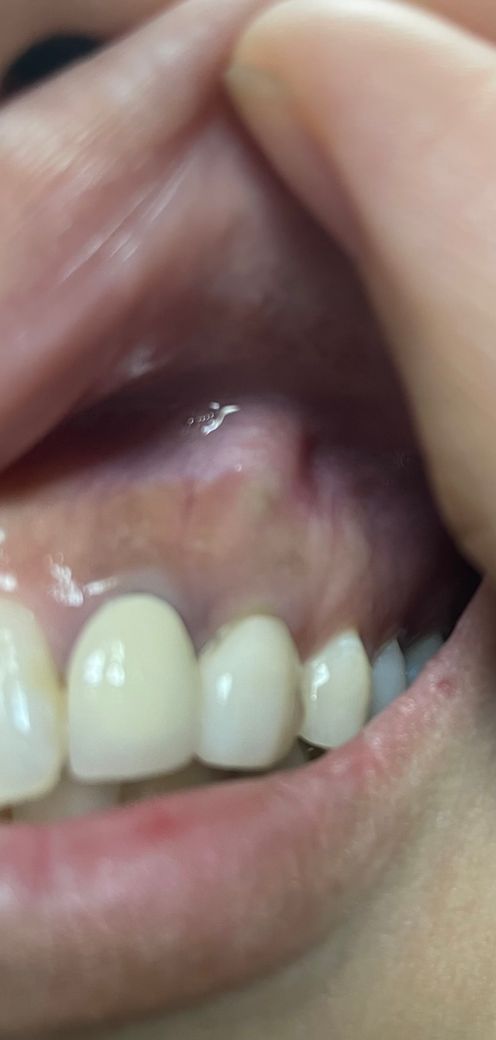

몇년전에 신경치료하고 크라운으로 씌운 치아 위쪽으로 사진처럼 뭐가 튀어나왔어요...

뼈인가요.,? 한번씩 미세하게 두근두근하는 증상이 있다가 없다가 합니다

통증이 있다기보단 신경쓰이는 느낌인데

심각한 건가요???

치아뿌리 끝에 염증이 생기게 되면 사진과 같이 해당 부위가 붙고 불편한 느낌이 있을 수 있습니다.

사진 상으로는 정확한 판단이 어렵습니다. 해당 부위가 염증으로 인하여 농이 찼을 수도 있고, 정상적인 뼈일 가능성도 있습니다. 다만 감각이 이상하다고 하셨으니 치과를 방문하여 해당 부위에 대한 검사를 하고 x-ray 등을 촬영하여 어떠한 것인지 감별 진단 받아보는 것이 중요할 것으로 보입니다.

뼈가 돌출이된 것인지 해당부위에 염증이 있어 잇몸이 부은 것인지 확인하기 위해서 치과에 방문하여 상태를 확인하고 치료를 받길 권합니다.

증식되어 돌출된 뼈가 맞는 것 같습니다. 통증이 없으니 큰 문제는 없을 것 같으나 계속 신경 쓰이신다면 치과를 내원해보시기 바랍니다.